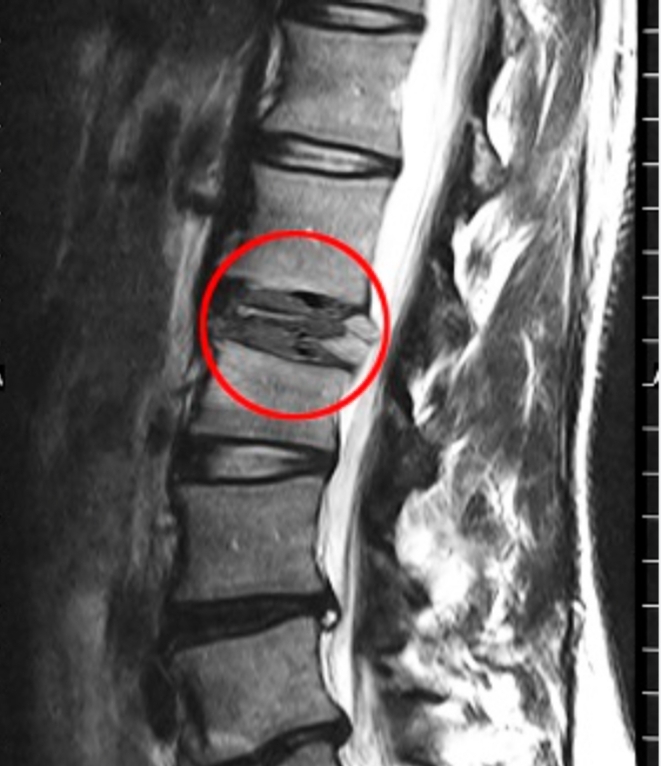

Bones are constantly being broken down and rebuilt. When disease disrupts this process, bone density decreases or the structure becomes abnormal. As a result, even minor stress can cause a fracture. These fractures often occur in the spine, hips, ribs, and long bones such as the femur.

Diagnosis usually involves imaging tests such as X-rays, CT scans, or MRIs to confirm the fracture. Bone density tests help detect osteoporosis, while blood tests can reveal infections or hormonal imbalances. A biopsy may be needed if cancer is suspected.